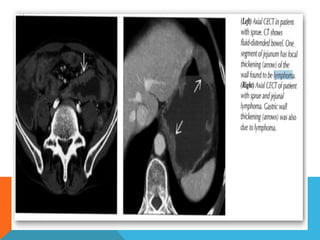

Small bowl  1/5of all small bowel malignancies.  Most common malignant small bowel tumor.   Multiple sites involvmentin1/5. Most common cause of INTUSSUSEPTION in children>6yrs

• 28.

 Location  ileum(51%) jejunum(47%)  duodenum(2%)  Site payer patches

• 29.

 Radiographic findings; Nodular pattern  Single mass  Infiltrating pattern  Exophytic  Mesenteric/retroperitoneal Adenopathy

Colon  Less ComonlyInvolved Than Stomach/Small Bowel 1.5% Of All Abdominal Lymphomas  Location Cecum Mostly  Presentation Single mass>diffuse infiltrating>polypoid Paradoxical dilatation Gross mural circumferential thickening Massive regional+distantmesenteric+retroperitoneum adenopathy.